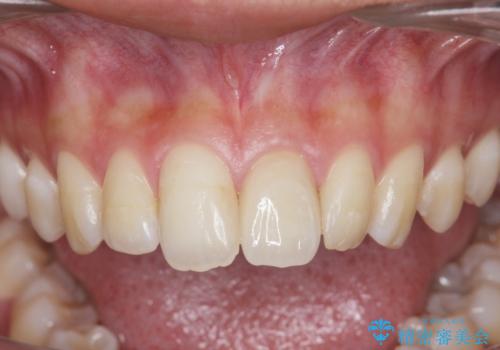

歯科技工士との綿密な打ち合わせで、非常に自然なセラミッククラウンを作製することができました。